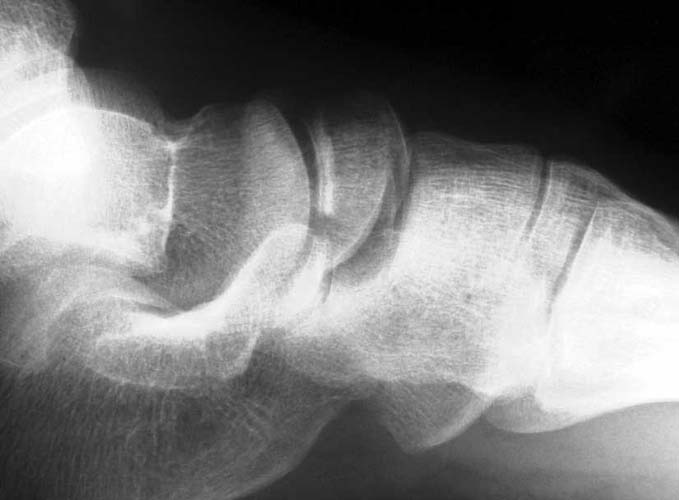

39yo male construction worker presents with 10 day old closed comminuted navicular # following low velocity fall from small motorcross bike.